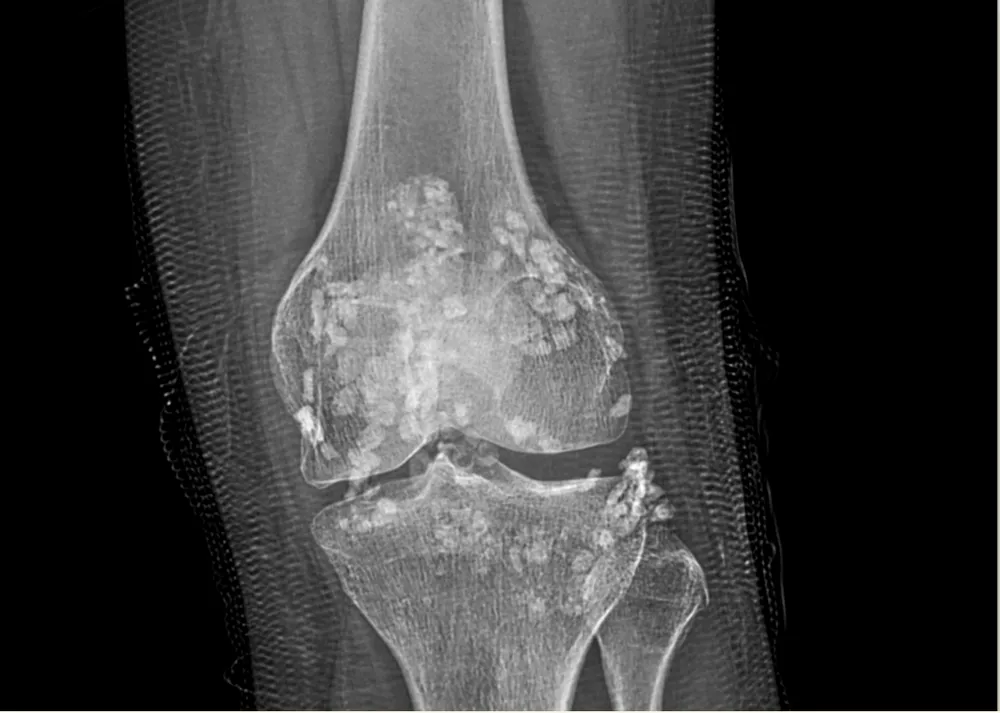

Kết quả thăm khám và thực hiện siêu âm, X quang cho thấy hình ảnh có rất nhiều nốt vôi hoá trong khớp gối.

Hình ảnh X quang cho thấy khớp gối bệnh nhân chứa đầy các nốt vôi hoá |

BS.CKI Nguyễn Ngô Dũng, đơn vị Cơ Xương Khớp, khoa Ngoại - Bệnh viện Gia đình Đà Nẵng cho biết, các nốt vôi hoá tồn tại trong bao hoạt dịch khớp gối trái kích thước khoảng từ 7-10mm và tập trung thành đám ở mô mềm vùng khoeo, kích thước đến 23*13mm chính là u sụn màng hoạt dịch, nguyên nhân chủ yếu gây ra cơn đau và cản trở vận động của bệnh nhân.